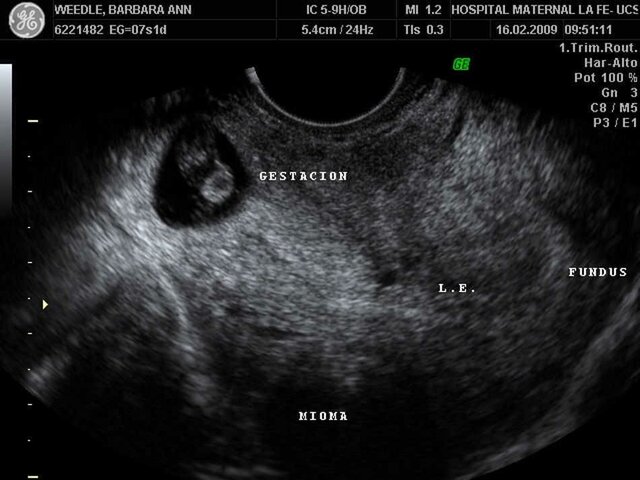

• ECO transvaginal

Se hace entre la 11va y 13ra semana para determinar la edad gestacional del embrión, estado del útero, y para valorar el pliegue nucal (Síndrome d Down).